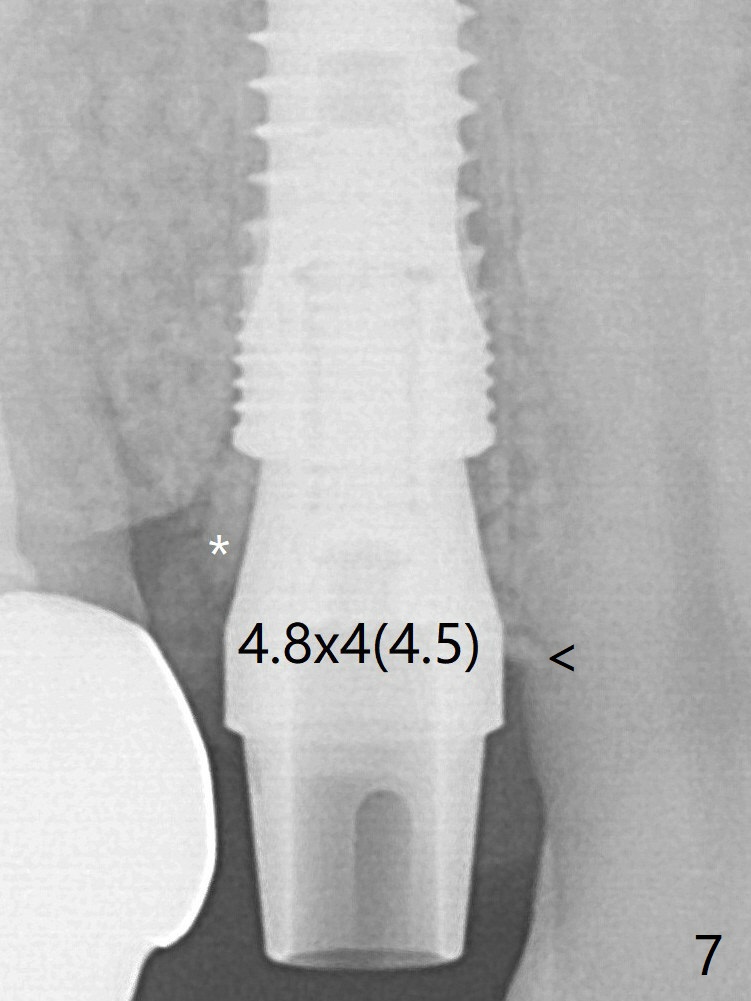

With the 2nd redirection (Fig.6 (4.5 mm tap, mesial crest (<) much lower than the distal one)), a 4.5x12 mm implant is placed with 50 Ncm; bone graft is placed with emphasis on the palatal defect (Fig.7 *). As usual, an immediate provisional is fabricated. In fact the abutment may be not completely seated because of contact with the mesial crest (<). After 5.5 mm profile drill 11 months postop, the abutment has no contact with the mesial crest (Fig.8 <).